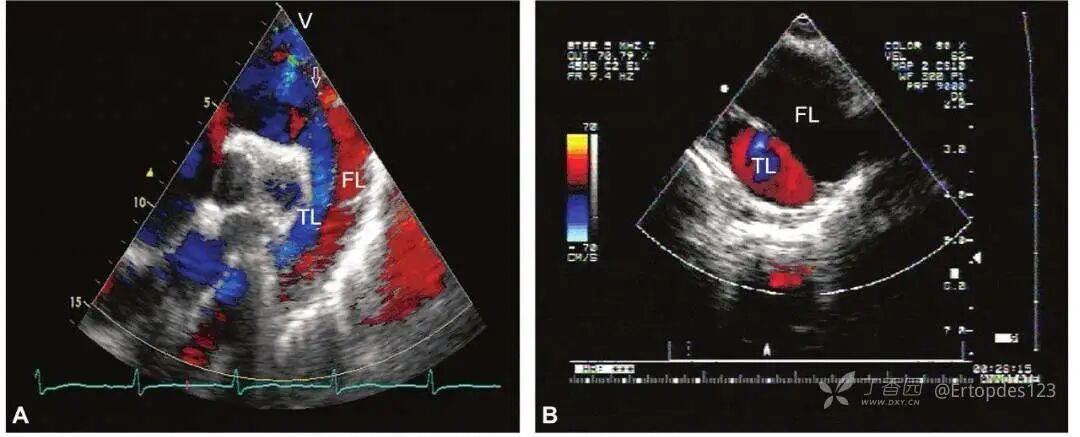

2.主动脉夹层彩色血流表现

A.胸骨上窝主动脉长轴切面显示升主动脉夹层,假腔与真腔内血流信号相反,假腔内血流呈红色且颜色暗淡,真腔内血流呈蓝色,颜色鲜艳;

B.大血管短轴切面显示撕裂的内膜将主动脉分为真、假两腔,真腔内血流呈红色,假腔内无血流信号显示;FL:假腔;TL:真腔